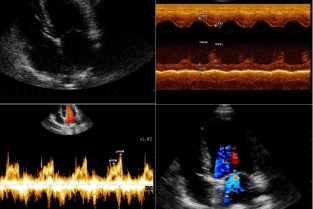

- d’effectuer de façon autonome une échocardiographie en réalisant sur des chiens, les principales coupes en mode BD et TM, et en faisant l’acquisition d’enregistrements Doppler.

- de pratiquer l’échocardiographie dans les principales cardiopathies acquises et congénitales des Carnivores domestiques.